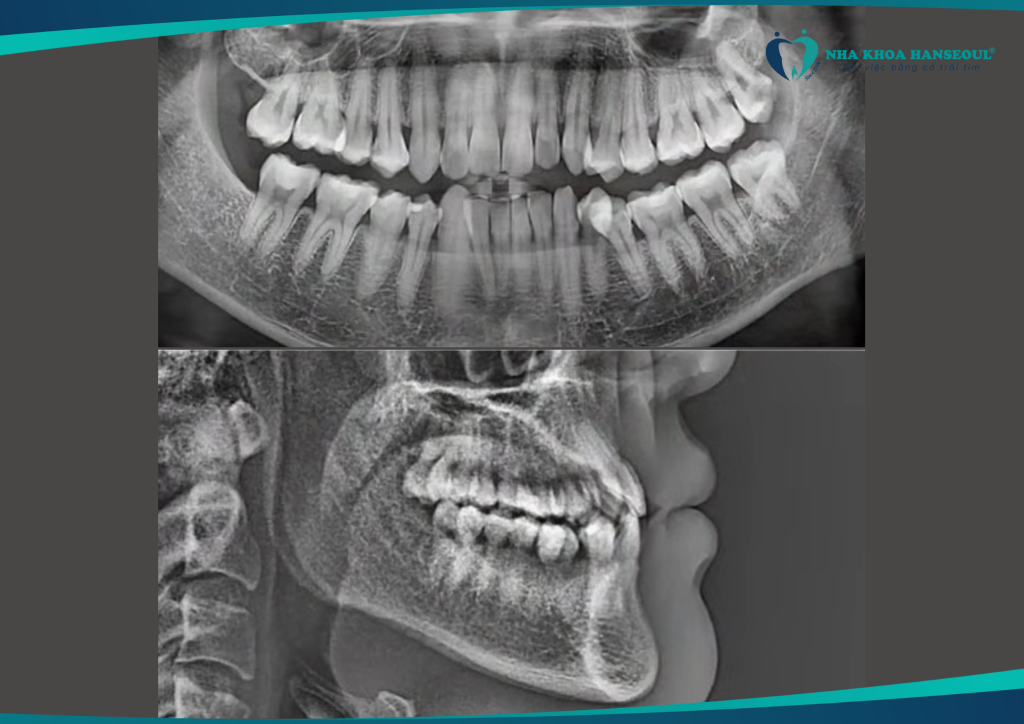

1 Tình trạng răng trước điều trị: Khớp cắn ngược hạng III móm, răng khôn sâu

Anh Trường gặp phải tình trạng khớp cắn ngược hạng III móm. Đây là một dạng sai khớp cắn khiến hàm dưới đưa ra trước. Ảnh hưởng đến cả chức năng ăn nhai lẫn thẩm mỹ khuôn mặt. Ngoài ra, anh còn gặp tình trạng răng khôn sâu, thường xuyên đau nhức. Ảnh hưởng lớn đến sinh hoạt hằng ngày.

Anh Trường đến với Nha khoa Hanseoul và được bác sĩ chuyên môn thăm khám, tư vấn kỹ lưỡng. Anh quyết định nhổ răng khôn, tiến hành niềng răng trong suốt Invisalign để cải thiện toàn diện tình trạng răng miệng.